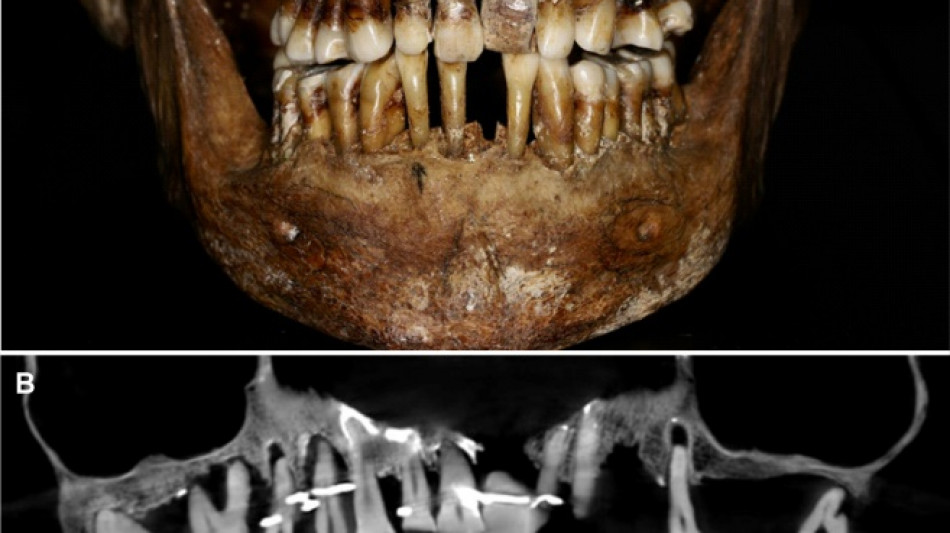

French aristocrat's golden dental secret revealed 400 years on / Photo: Handout - INRAP/Rozenn Colleter/AFP/File

Embalmed in a lead coffin, her skeleton -- and teeth -- were remarkably well preserved.

At the time the archaeologists noticed that she had a dental prosthetic, but they did not have advanced scanning tools to find out more.

Thirty-five years later, a team of archaeologists and dentists have identified that d'Alegre suffered from periodontal disease that was loosening her teeth, according to a study published in the Journal of Archaeological Science: Reports this week.

A "Cone Beam" scan, which uses X-rays to build three-dimensional images, showed that gold wire had been used to hold together and tighten several of her teeth.

She also had an artificial tooth made of ivory from an elephant -- not hippopotamus, which was popular at the time.